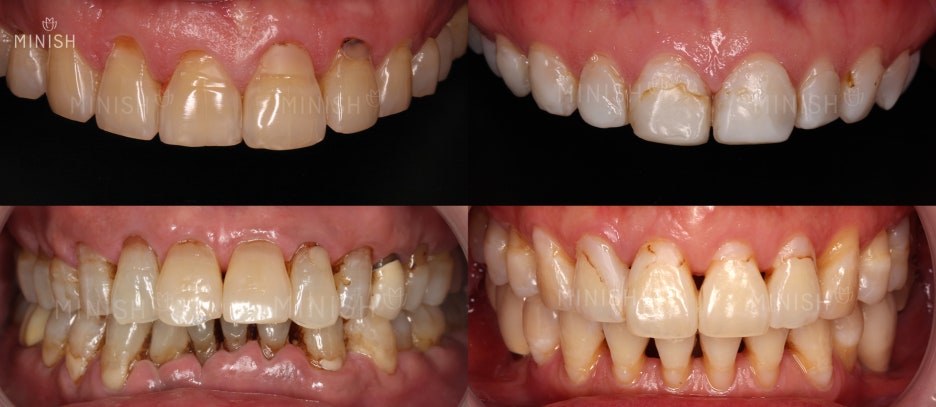

◼ 질환 : 치주염, 블랙트라이앵글, 벌어진치아

◼ 촬영일자 : 2018.08.27 | 2018.08.28

◼ 실치료기간 : 1일

- 개인에 따라 치료 기간이 다를 수 있으며, 부작용이 발생할 수 있으니 의료진의 정확한 진료를 받고 치료를 진행하시기 바랍니다.

미니쉬는 치면을 코팅, 치은을 대신해서 보호막 역할을 합니다.

외부자극을 막아 시린이 증상을 막고, 음식물이 끼기 쉬운 블랙트라이앵글도 막아 건강한 구강 환경을 만듭니다. 자연치아와 강도, 색상, 투명도가 유사한 재료를 사용해 관리 방법까지 닮아있습니다. 까다로운 관리 없이도 오래 유지되는 치료로 불릴 수 있는 이유죠.